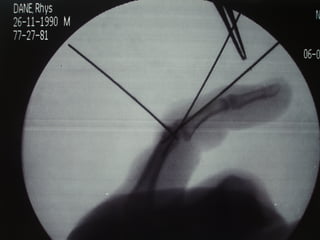

ď‚§ Operative Mx:

ď‚§   Debridement & joint washout for open injuries

ď‚§   Dorsal block splinting

ď‚§   ? Role of primary VP repair

ď‚§   Other specific techniques for unstable PIPJ injuries:

ď‚§   Dynamic skeletal traction

ď‚§   Extension block pinning

ď‚§   Trans-articular pinning

ď‚§   ORIF

ď‚§   Volar plate arthroplasty

ď‚§   FDS tenodesis (for chronic hyperextension deformity of PIPJ)

Dorsal PIPJ Dislocations ď‚§Operative Mx: ď‚§ Debridement & joint washout for open injuries ď‚§ Dorsal block splinting ď‚§ ? Role of primary VP repair ď‚§ Other specific techniques for unstable PIPJ injuries: ď‚§ Dynamic skeletal traction ď‚§ Extension block pinning ď‚§ Trans-articular pinning ď‚§ ORIF ď‚§ Volar plate arthroplasty ď‚§ FDS tenodesis (for chronic hyperextension deformity of PIPJ)